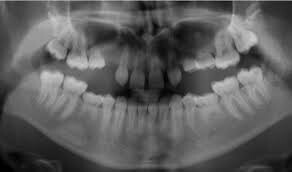

What Are Congenitally Missing Teeth

Congenitally missing teeth or hypodontia is a condition where some of the adult teeth do not develop. Although it can also affect the primary teeth, this is quite rare, unless there is an underlying genetic disorder.

What teeth are usually affected?

Third molars (wisdom teeth) are the most commonly missing but are not included in the definition of hypodontia. This is because it is considered a variation of normal to have missing wisdom teeth. The other most commonly missing teeth are lower second premolars and the upper lateral incisors.

How will I know if I have missing teeth?

Your dental professional will be able to tell if you have any missing teeth. Usually, they will need an x-ray to confirm this. Gaps between your teeth, losing a baby tooth with no adult tooth taking its place or having a baby tooth longer than normal are all signs of having congenitally missing teeth.